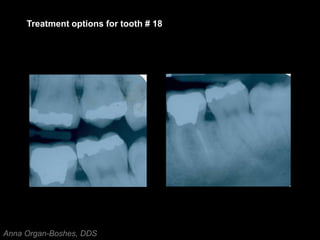

Treatment options for tooth # 18

Treatment options fortooth # 18 Anna Organ-Boshes, DDS